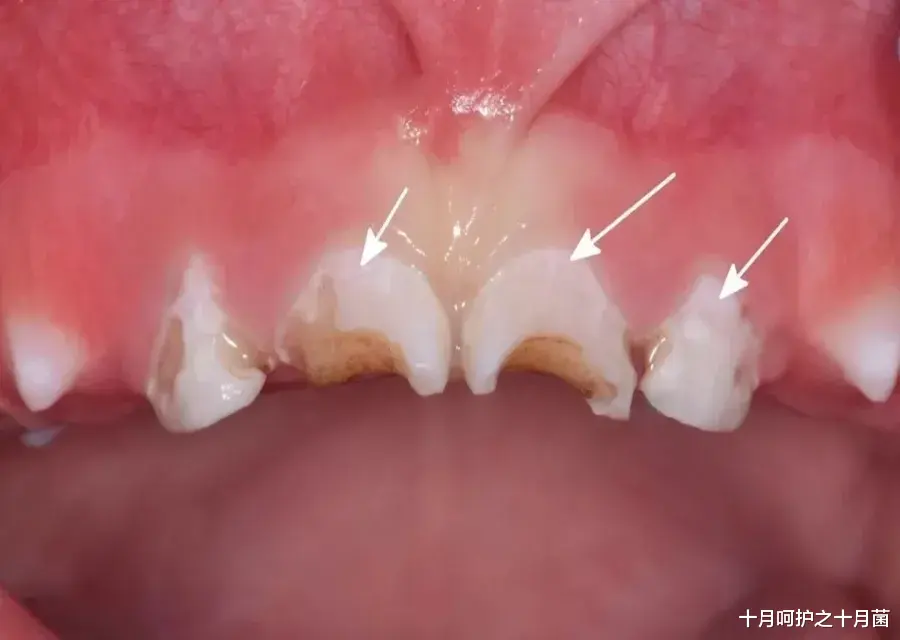

◆ 牙齿脱矿是什么?

牙齿脱矿是指牙釉质被细菌产生的“酸”所溶解 , 导致钙离子流失、釉质结构变疏松的过程 。

脱矿的部位 , 一般表现为白色粉笔状的不透明斑块 。

如果不及时处理 , 随着脱矿过程的不断进展 , 釉质结构最终会被破坏 , 形成龋洞 。

牙齿脱矿和缺钙无关 , 而是糖和细菌侵蚀牙齿所导致的 。

因此 , 想要预防牙齿脱矿 , 一定要注意宝宝牙齿的日常清洁 。